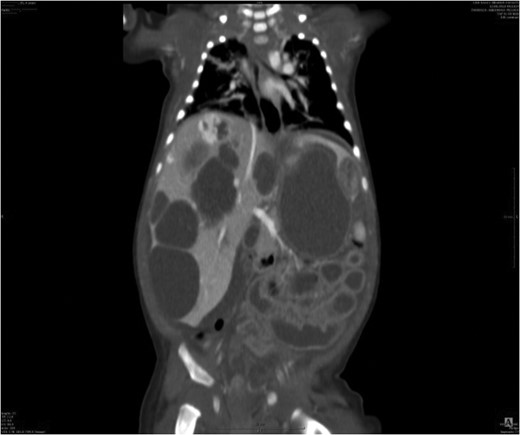

Medical treatment was started immediately with intravenous corticoids (2 mg/kg/day) accompanied with beta-blockers (propranolol 2 mg/kg/day). Ultrasound and CT scans performed after 6 months showed scattered liver parenchymal invaded by multiple enlarging cysts varied in sizes and shapes and causing severe abdominal compression (Fig. 3).

Liver parenchyma invaded by multiple enlarging cysts varied in sizes and shapes.